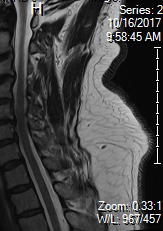

67 yo guy

Totally normal, reasonable, very high functioning professional.

Has been having left arm radicular pain for several months. Noticing some weakness in the last month or two. Hard to carry books, drooped a few things etc. On exam some subtle weakness of grip strength/hand on that side, but still like 4.5/5.

MRI below. I measured the AP canal diameter at that tightest level at around 9mm.

Has not done cervical traction/gabapentin or CESI.

Surgeon has him on for mid Decemeber for what sounds like a fusion. Said no point doing other stuff as surgery is going to have to happen.

What do you guys think? He is asking me if I would just have the surgery or try and hold off.

Seems like a tweener...

FINDINGS:

There is normal alignment without evidence of acute fracture or dislocation. Vertebral body heights are well maintained. Visualized cord is within normal limits. Normal marrow signal. Prevertebral soft tissues are unremarkable.

Individual disc levels are as follows:

C2-C3: Small posterior disc osteophyte complex and bilateral facet arthropathy resulting in mild spinal canal narrowing. There is mild bilateral neural foraminal narrowing.

C3-C4: Small posterior disc osteophyte complex with right lateral recess component and mild facet arthropathy resulting in mild to moderate spinal canal narrowing. There is moderate bilateral neural foraminal narrowing.

C4-C5: Small to moderate posterior disc osteophyte complex with right paracentral and lateral recess component resulting in moderate spinal canal narrowing and deformation of the ventral cord. There is moderate to severe right and mild left neural

foraminal narrowing.

C5-C6: Moderate posterior disc osteophyte complex and bilateral facet arthropathy resulting in severe spinal canal narrowing. There is severe right and moderate to severe left neural foraminal narrowing.

C6-C7: Moderate posterior disc osteophyte complex and bilateral facet arthropathy resulting in moderate to severe spinal canal narrowing. There is moderate to severe right and moderate left neural foraminal narrowing.

C7-T1: Mild disc desiccation without significant spinal canal or neural foraminal narrowing.

IMPRESSION:

Multilevel degenerative changes of the cervical spine as described, most pronounced at C5-C6 with severe spinal canal stenosis.

Neural foraminal stenosis as described.

There is CSF on both sides in the sagittal cuts and there is no contouring of the cord at all.

What level is your axial slice? C5-6? And yeah if he doesn't have any long track signs I wouldn't get too excited. In fact I see cervical spines like this all time here at the VA and the surgeon almost always wants to watch them. Then again he's not getting paid per surgery like your guy 😉

No signal in cord..not myelopathic..doesn't need decompression yet. I would treat with pt, nsaids, low volume cesi. Obvi discuss how cervical spondylitic myelopathy can present with stepwise neurological decline...

If the AP diameter is 9mm, it cannot be severe stenosis unless the cord itself is enlarged at that level- it does not appear to be. I agree with others that there is not severe central stenosis, and that this is an over-read or misread by the radiologist. The misinterpretation by the radiologist accompanied by some symptoms that may be attributable to foraminal stenosis may be prompting the surgeon to move (inappropriately) directly to surgery. However, there are not any other significant medical or alternative medicine techniques that will undo foraminal stenosis, so it is somewhat of a judgement call about when to pull the trigger.